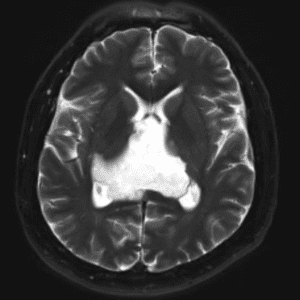

Case #14

CNS toxoplasmosis